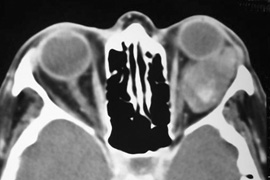

Fig. 16. A. Patient with right orbital cellulitis. B. Coronal CT scan demonstrating subperiosteal abscess formation from frontal and ethmoidal sinusitis. C. Frontoethmoidal orbitotomy incision marked for abscess drainage.

The periosteum is exposed and incised with a Freer elevator and then is reflected off the bone posteriorly. It is generally quite adherent to the curved contour of the medial canthal bones, especially at the medial canthal tendon. The anterior lacrimal crest is encountered inferiorly. Care should be taken not to damage the lacrimal sac with the elevator. The posterior lacrimal crest is visible behind the sac. Adequate mobilization of the periosteal connections to the anterior lacrimal crest gives a large area of exposure. The periosteal elevation is carried superiorly in the area of the trochlea. Elevation of the periosteum opens the subperiosteal space. Blood or pus caused by fracture or infection, if present in this space, is encountered at this point.

Elevation of the periorbita along the medial orbital wall posterior to the lacrimal sac progresses easily. Orbital fractures involving the thin ethmoid bone are seen at this point. The anterior ethmoidal artery is seen at the junction of the ethmoidal and frontal bones where the orbital roof meets the medial orbital wall (see Fig. 7). Usually it is found on a line extending posteriorly from the superior border of the medial canthal tendon. This artery either should be thoroughly cauterized with the bipolar cautery or clipped with a vascular clip before cutting. As the dissection in the subperiosteal space moves posteriorly, the orbit narrows. The posterior ethmoidal artery is identified. This is a reliable landmark for the optic foramen, which lies approximately 5 mm behind the ethmoidal artery.

Indications

The frontoethmoidal medial orbitotomy allows access for a variety of procedures in the subperiosteal and peripheral surgical spaces and sinuses (Fig. 17). Its main use is for processes involving both the frontal or ethmoid sinuses and the orbit. Entrance into the subperiosteal space is obtained easily. Drainage of subperiosteal blood or pus occurs as the space is entered.